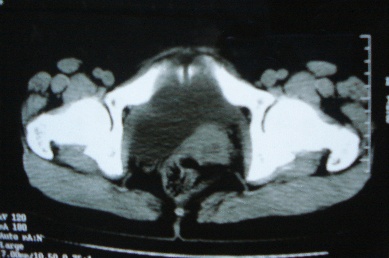

标题: CT8388:女,48岁。感腹胀一周,请会诊

ct10755,女,48岁。感腹胀一周入院。

考虑右侧卵巢囊腺癌并腹腔转移、子宫肌瘤

支持右侧卵巢囊腺癌并腹腔转移

考虑右侧卵巢囊腺癌并腹腔转移可能性大、子宫肌瘤

支持:右侧卵巢囊腺癌并腹腔转移,或囊腺瘤破裂腹腔种植。

支持:右侧卵巢囊腺癌并腹腔转移、腹水、盆腔积液。